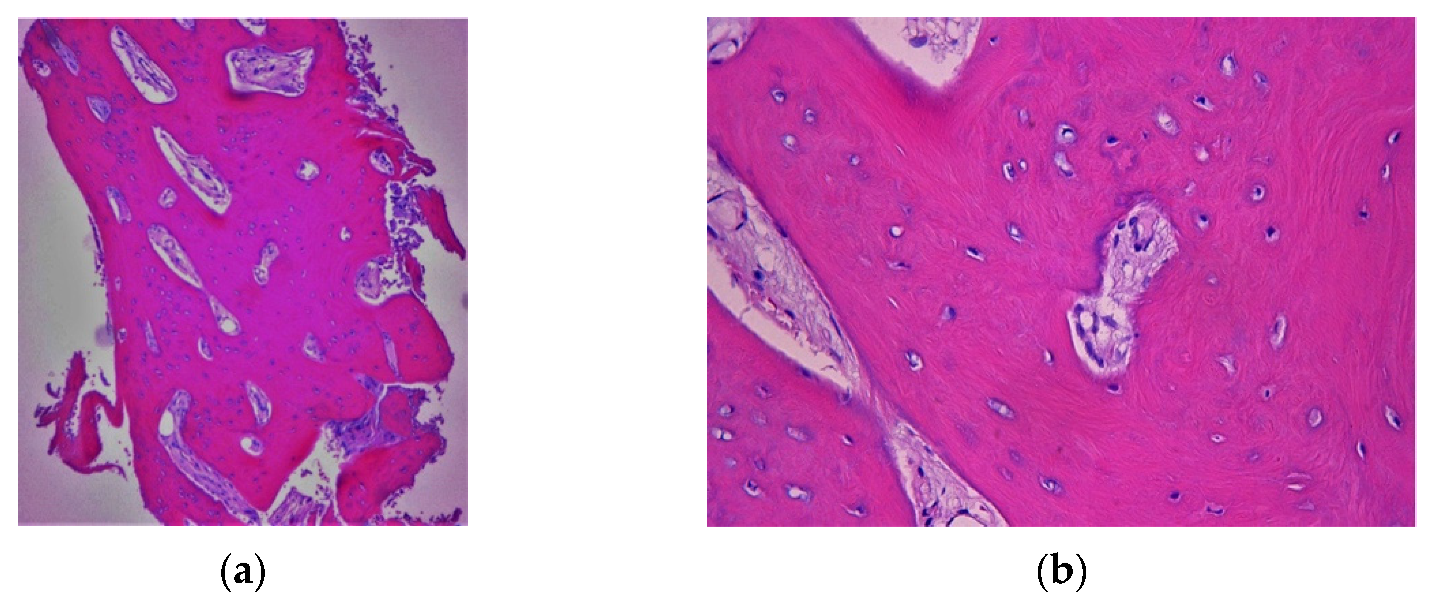

4.1. Clinical Case n.1.

4.2. Clinical Case n.2.

4.3. Clinical Case n.3.

4.4. Clinical Case n.4.

4.5. Clinical Case n.5.